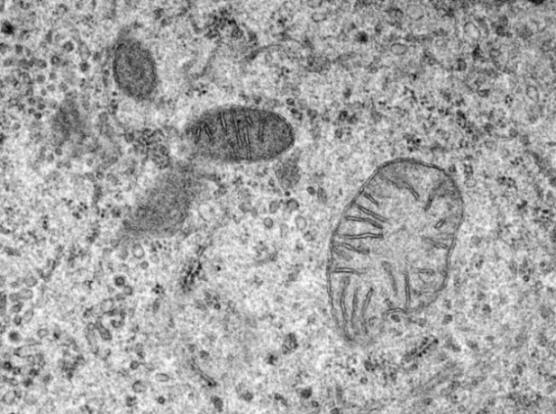

8. Come funzionano i mitocondri?

I mitocondri sono parte integrante del nostro corpo. Il solo scopo degli organelli microscopici è trasformare tutto il cibo che consumiamo in energia. Per molto tempo non lo sapevamo i mitocondri non sono quasi nulla, ma la scienza è vicina a capire come funzionano.

Più recentemente, gli scienziati hanno imparato come i mitocondri trasportano energia. Gli scienziati hanno anche imparato che ai mitocondri piace molto il calcio, che a volte può causare problemi: se i mitocondri assorbono troppo calcio, può uccidere le cellule. Ciò è dovuto a malattie come il diabete di tipo 2.

I ricercatori ritengono che queste malattie colpiscano il processo di trasmissione dei segnali attraverso il quale il corpo comunica mitocondri, quanto calcio viene assorbito e quanto viene escreto. Un team di ricerca di Harvard è riuscito recentemente a coinvolgere catalogare ogni proteina nei mitocondri, comprese tutte le proteine, associato all’assorbimento del calcio. Finora, ci sono poche informazioni, ma questo stiamo per risolvere il mistero.